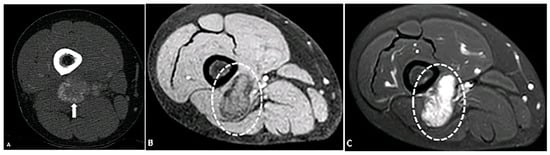

5.7. Cysticercosis

- Nepal, P.; Ojili, V. Rice-grain calcifications of cysticercosis. Abdom. Radiol. 2021, 46, 1276–1277. [Google Scholar] [CrossRef]

- Meena, D.; Gupta, M.; Jain, V.K.; Arya, R.K. Isolated intramuscular cysticercosis: Clinicopathological features, diagnosis and management–A review. J. Clin. Orthop. Trauma 2016, 7, 243–249. [Google Scholar] [CrossRef]

- Liu, H.; Juan, Y.-H.; Wang, W.; Liang, C.; Zhou, H.; Ghonge, N.P.; Saboo, S.S. Intramuscular cysticercosis: Starry sky appearance. QJM Int. J. Med. 2014, 107, 459–461. [Google Scholar] [CrossRef]